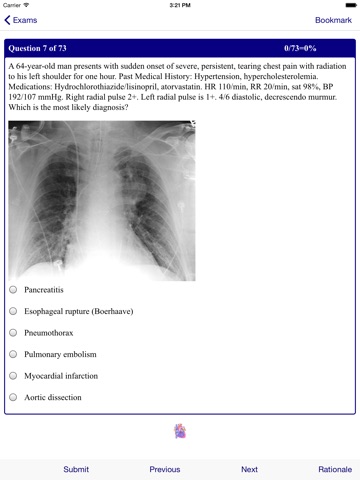

Emergency Medicine Review Emergency Medicine Review provides the full spectrum of emergency medicine at your fingertips on your iPhone device. Includes 300 Emergency Medicine Board clinical scenario review questions. NOW IN COLOR Written by clinicians engaged in the day-to-day practice of emergency medicine, this app is the most trusted app in emergency care. Composed of brief chapters focusing on clinical features, diagnosis, and emergency management, Emergency Medicine Review is designed to help you provide skillful and rapid patient care. This expanded and revised app is enhanced by: A full color design with photos and drawings Numerous tables, making information easy to access Completely revised and reorganized content to match current practice New chapters on Acute Coronary Syndromes, Thromboembolism, Occlusive Arterial Disease, Nausea and Vomiting, Trauma, and Bowel Obstruction and Volvulus. With its unmatched authority and easy-to-use organization, Emergency Medicine Review belongs in the pocket of every clinician working in acute medical care.

Poorly designed. Images associated with cases do not correspond. The rationale for management questions do not make sense; correct answer is not revealed. Complete waste of money.